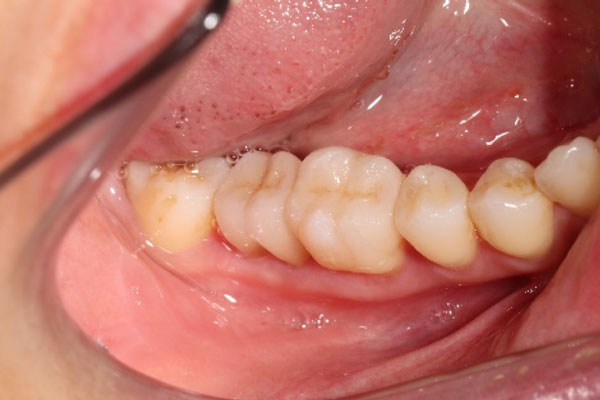

支台築造(土台・コア)ファイバーコア・ファイバーポストについて

ファイバーコア(ポスト)とは、根の治療(根管治療)をした歯に必要な、歯を補強する治療です。

神経を取った歯は、補綴治療「かぶせ物(クラウン)」をしなくてはいけません。その際に残っている歯に、土台(コア)を建てることを支台築造と言います。

土台が出来上がった歯には写真のように作られた「かぶせ物(クラウン)」が入りますので、かぶせ物をセットして治療が終了します。

その土台の内部にグラスファイバー繊維(ファイバーコア・ポスト)を使うことで、歯を補強し、破折(歯が割れない・折れない)ようにするのがファイバーを使った支台築造です。

当院で行う支台築造はラバーダムを使用し細菌感染をなくし、歯に精密に埋めることで歯とファイバーが一体化し、歯への負担を減らすことが可能となります。

精度の高い支台築造を提供できます。

作られたセラミック歯

かぶせたセラミック歯